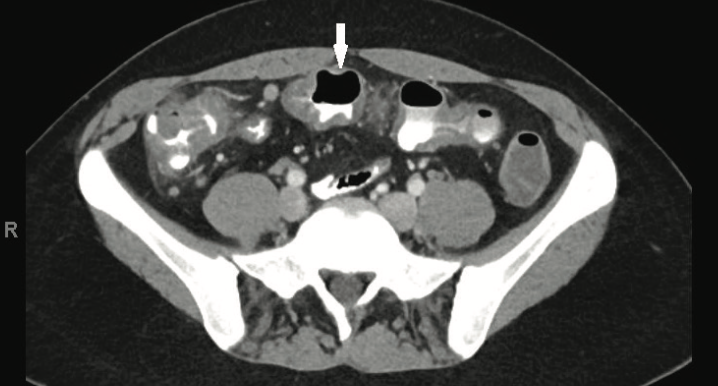

Brandon M. Carius, PA-C; Ronald D. Anderson, DO; Brian K. White, DO

A 36-year-old man serving in the military presented with persistent right upper quadrant abdominal pain.

09/18/2018